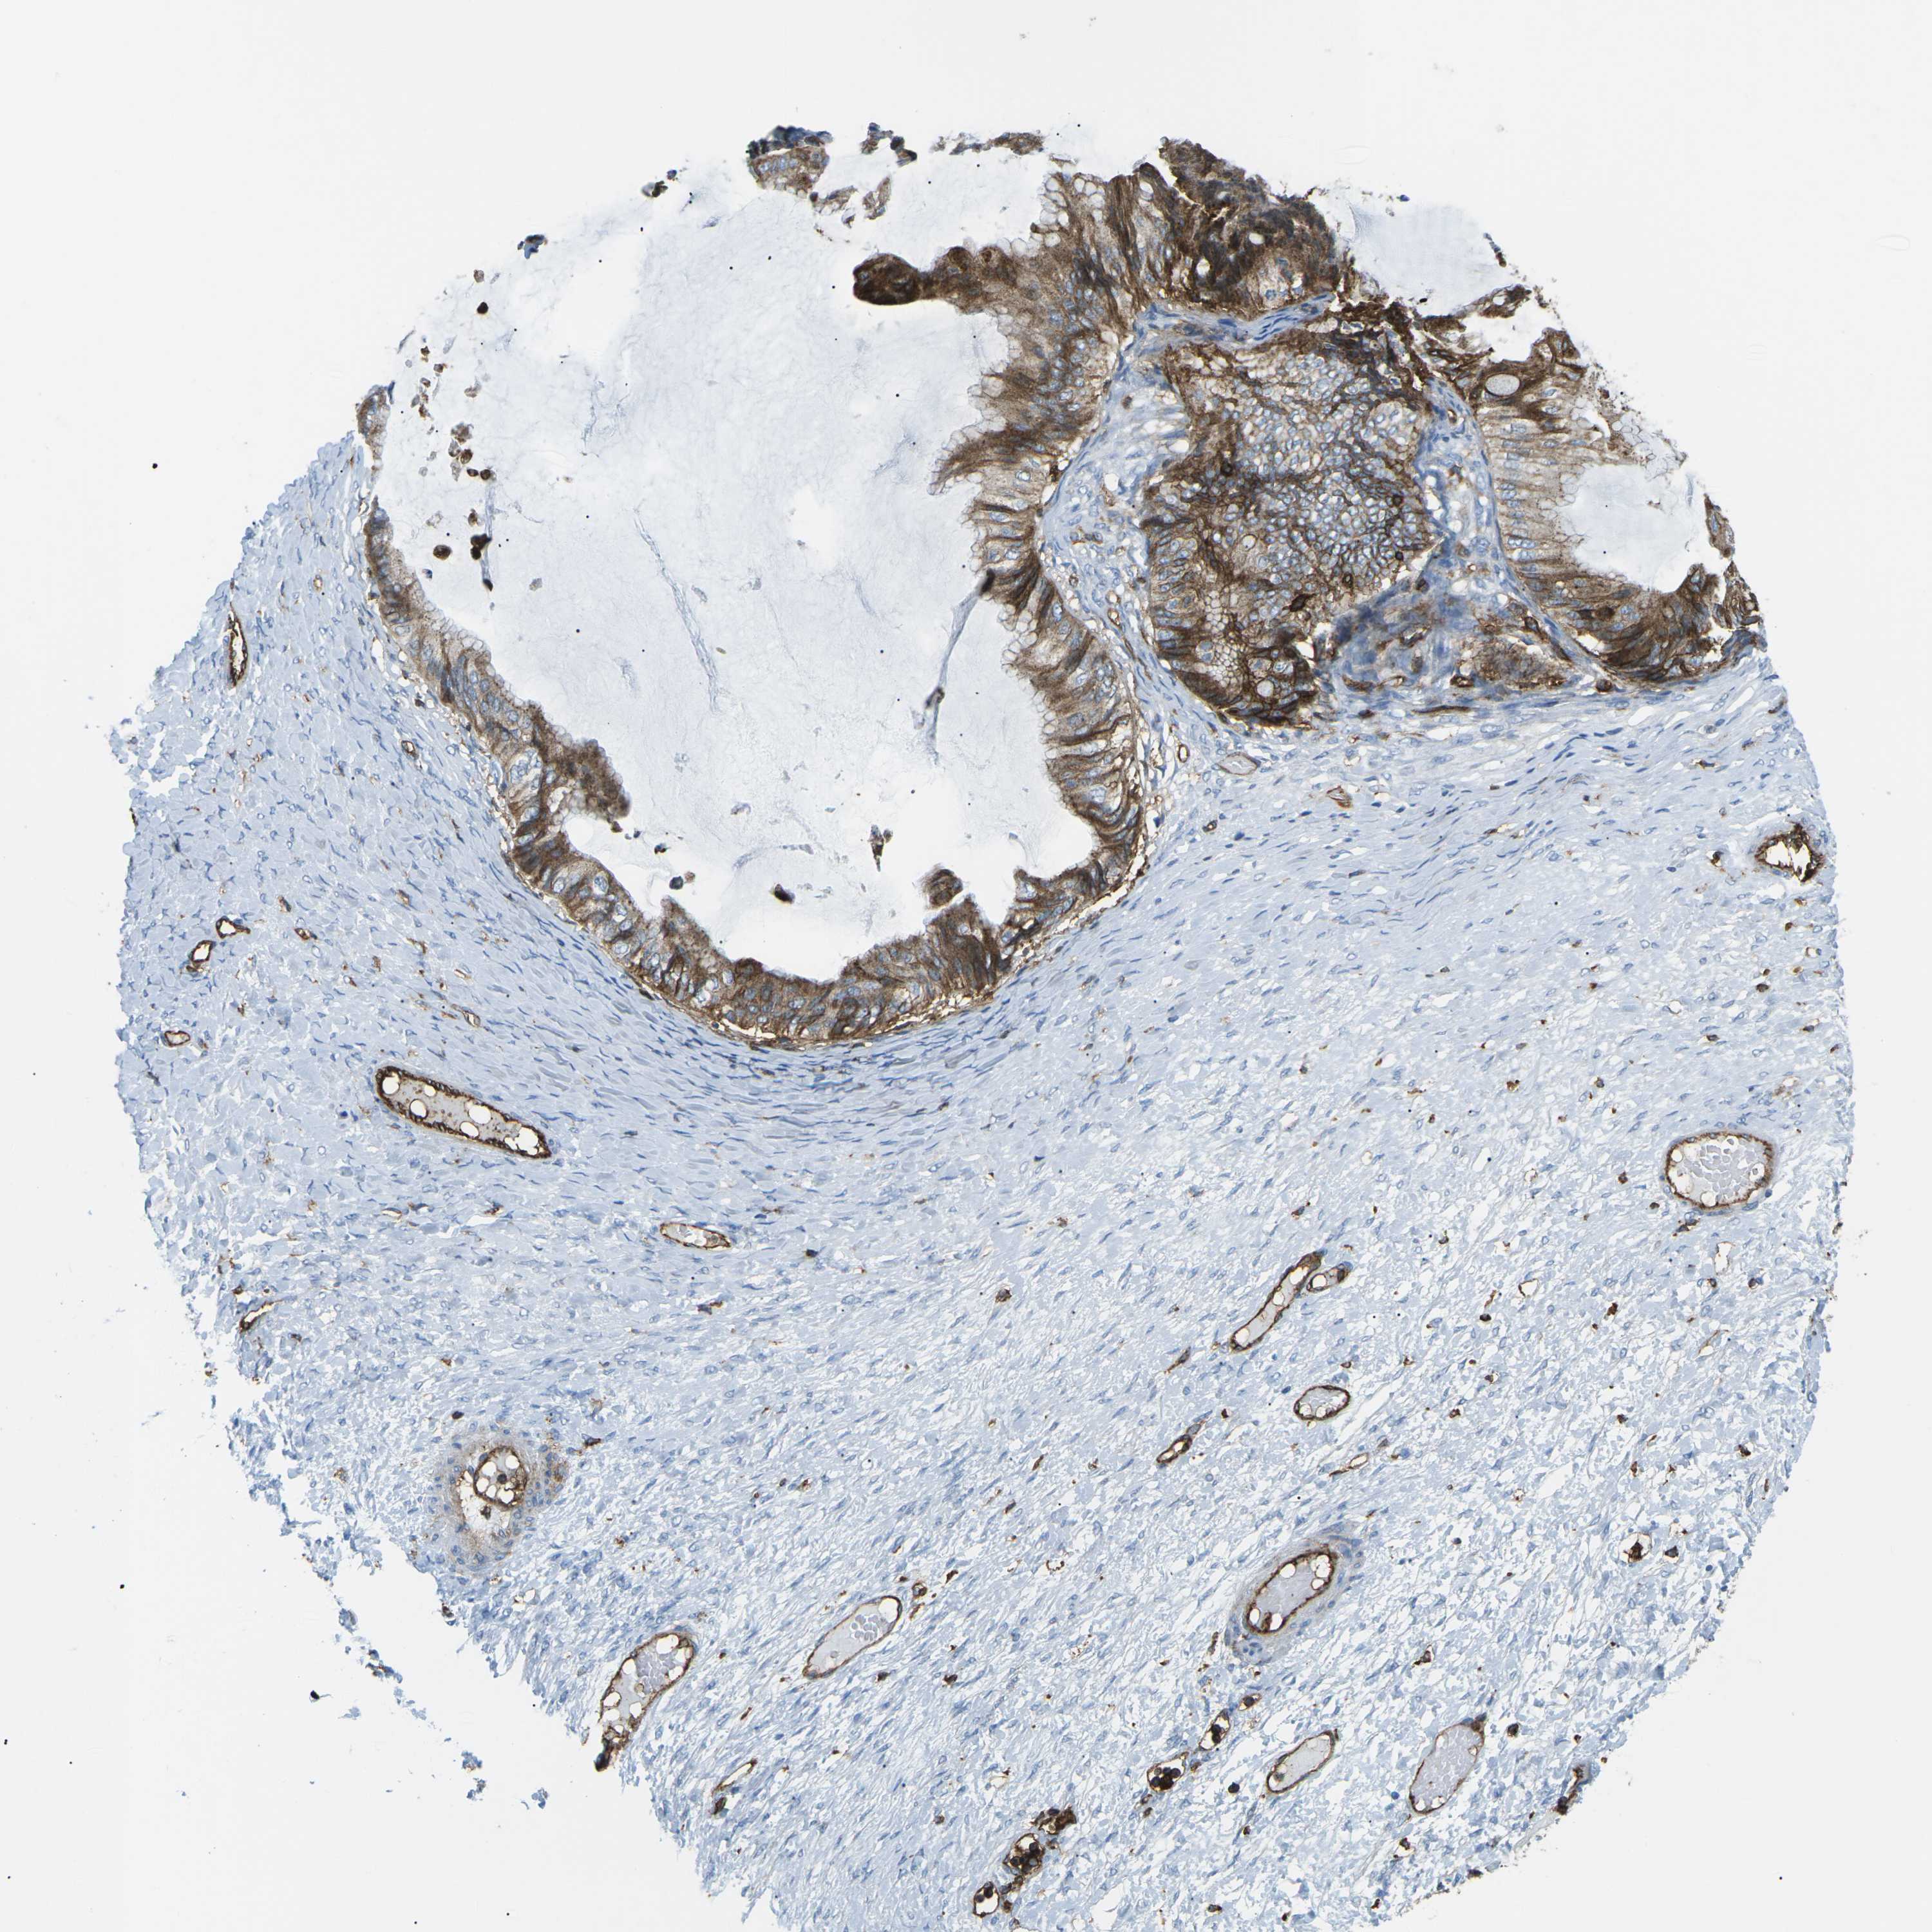

OVARIAN CANCER - Protein expressioni

A mouse-over function shows sample information and annotation data. Click on an image to view it in a full screen mode. Samples can be filtered based on level of antibody staining by selecting one or several of the following categories: high, medium, low and not detected. The assay and annotation is described here.

Note that samples used for immunohistochemistry by the Human Protein Atlas do not correspond to samples in the TCGA dataset.

Antibody stainingi

Antibody staining in the annotated cell types in the current human tissue is reported as not detected, low, medium, or high, based on conventional immunohistochemistry profiling in selected tissues. This score is based on the combination of the staining intensity and fraction of stained cells.

Each image is clickable and will lead to virtual microscopy that enables deeper exploration of all samples and also displays staining intensity scores, fraction scores and subcellular localization as well as patient and tissue information for each sample.

Antibody CAB015418

Staining

Cystadenocarcinoma, serous, NOS

Carcinoma, endometroid

Cystadenocarcinoma, mucinous, NOS

Carcinoma, NOS